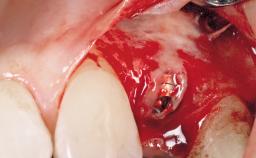

Immediate Flapless Placement of an Implant in a Maxillary Left Central Incisor Site

A 29-year-old female patient presented for treatment to replace the upper left central incisor tooth with an implant- supported restoration. The tooth had been intermittently symptomatic for the previous 12 months. The tooth had originally suffered trauma about 15 years previously. Several endodontic treatments had been performed, including an apicectomy procedure to retain the tooth. The patient was healthy and a non-smoker. She had reasonable expectations in regard to esthetic outcomes and the risk of marginal tissue recession following treatment. At medium smile, the gingival margins of the upper teeth were visible, with a display of 3 to 4 mm of the gingival margins. Gingival recession of tooth 21 and a discrepancy in the gingival levels between teeth 11 and 21 was observable during normal speech and smile.

Type of Implants One-Piece

Placement Protocol Immediate implant placement

Socket Integrity Damage to one or more bone walls

Bone Volume Damage to one or more socket walls